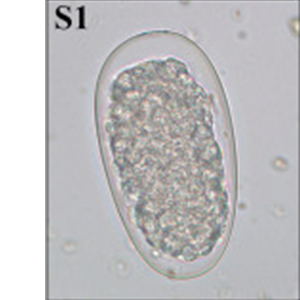

Les œufs de strongle présentent globalement la même morphologie ; ce sont des œufs ovalaires, à paroi lisse, possédant une morula et des faces latérales non parallèles. Leur taille est très variable (40 x 60 μm à 110 x 230 μm) et les groupes évoqués ci-dessus peuvent présenter des caractéristiques permettant d’orienter le diagnostic mais ces dernières sont à prendre avec précaution. Ces œufs, lorsqu’ils persistent longtemps dans le milieu extérieur, peuvent présenter un embryon vermiforme (Garcia, 2021).

- Les anguillules(Strongyloides): ces nématodes rentrent dans le diagnostic différentiel des œufs de strongle embryonnés. A l’inverse des œufs de strongles, ils mesurent 40-70 μm de longueur pour 20-35 μm de largeur, possèdent une paroi très fine et leurs faces latérales sont parallèles (Garcia, 2021).